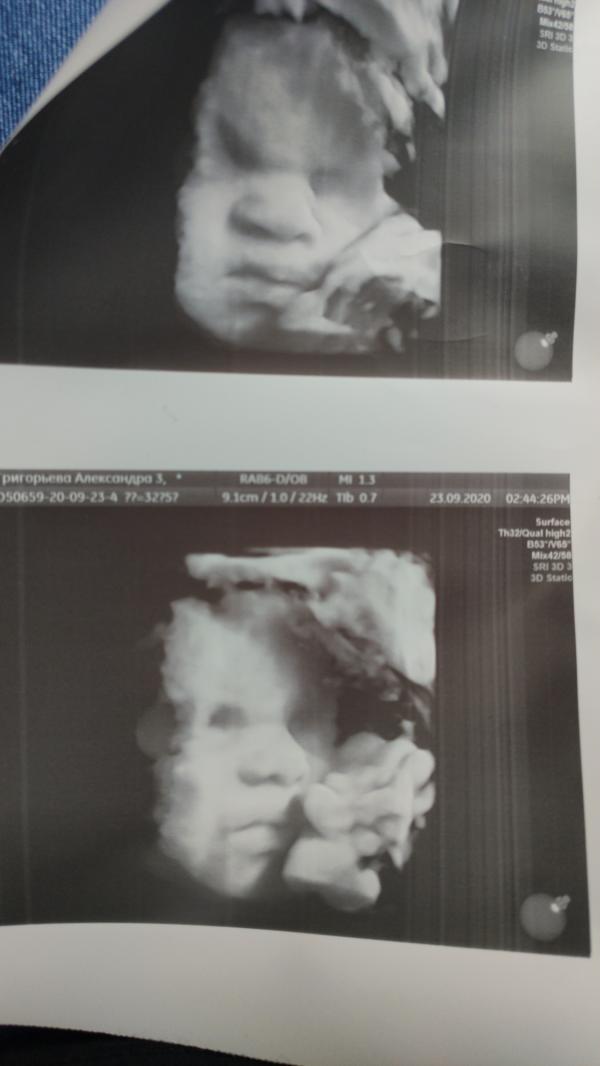

📆 ПДР - 09.11.2020

🗓 Срок на момент родов - 41 недель 6 дней